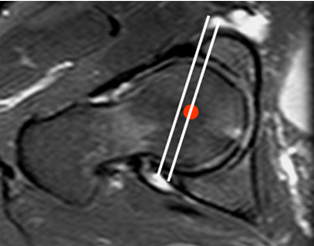

Con RM se puede valorar en un corte axial oblicuo. Se traza una línea que una el reborde oseo anterior y posterior y otra línea paralela a esta, que pase por el centro de la cabeza femoral. Normalmente la línea del centro femoral, tiene localización lateral. En los casos de coxa profunda, la línea se localiza medialmente. (Fig 95 y 96).

Fig 96. Coxa profunda.

RM axial oblicua. La paralela al centro de la cabeza femoral se localiza medial, a la línea que une el reborde acetabular oseo anterior y posterior.